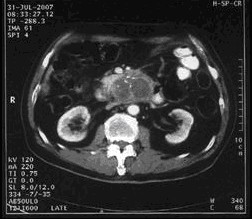

男,68歲,2006年12月14日,CT掃描發(fā)現(xiàn)胰頭占位性病變,6.0×4.7cm2,腹膜后淋巴結(jié)轉(zhuǎn)移,伴肝內(nèi)多發(fā)轉(zhuǎn)移灶。艾恒+希羅達(dá)化療3療程無效(圖1)。2007年4月5日,開始接受今又生治療,胰腺腫瘤內(nèi)注射今又生1×1012VP,共2次,結(jié)合放療45Gy/10f(圖2)。2007年5月12日,IMA64+C,5.3×3.5=18.6cm2,縮小41.0%,瘤囊性化。腹腔灌注今又生5次,1-2×1012VP/次/周,+順鉑60mg,健擇每周1.4g,治療2周。療后1年,腫瘤進(jìn)一步縮小及壞死(圖3)。

治療前